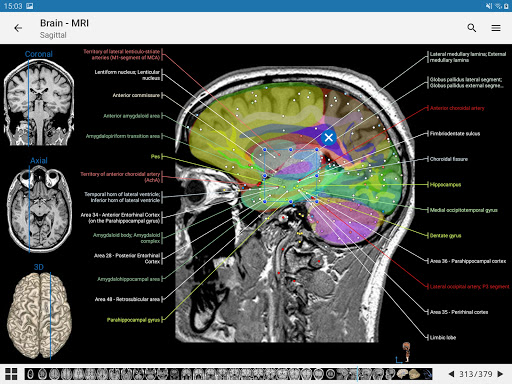

e-Anatomy tiene más de 26 000 imágenes que contienen series de imágenes en vistas axiales, coronales y sagitales, así como radiografías, angiografías, imágenes de disección, gráficos anatómicos e ilustraciones. Todas las imágenes médicas fueron etiquetadas cuidadosamente, más de 967 000 etiquetas disponibles en 12 idiomas, incluida la Terminologia Anatomica latina.

- Toque las etiquetas para mostrar las estructuras anatómicas

- Seleccione las etiquetas anatómicas por categoría

- Localice fácilmente las estructuras anatómicas gracias a la búsqueda de índice

-El modo pines tiene un nuevo comportamiento que le permite seguir una estructura anatómica mucho más fácilmente

-Ahora puede seleccionar manualmente el tamaño de fuente que prefiere para sus etiquetas de estructuras anatómicas (en modo etiquetas)

-Dentro de la vista de detalles de una estructura anatómica , un alfiler ahora señala la estructura relacionada en todas las imágenes presentes